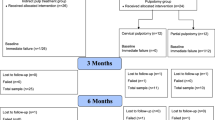

Two methods were employed in this study. First, a finite element (FE) model was constructed, which included alveolar bone, the first premolars extracted maxillary dentition, periodontal ligaments (PDL), attachments and aligners. The second method involved an experimental model—a measuring device using multi-axis transducers and vacuum thermoforming aligners. Two groups were formed: (1) The control group used common CAs and (2) the enhanced structure group used partially thickened CAs.

A healthy adult with well-aligned complete dentition was selected as the subject for this study. Based on cone-beam computed tomography (CBCT) data, the three-dimensional model of alveolar bone and the maxillary dentition with the extraction of the first premolars were reconstructed using Mimics Research 21.0 (Materialize, Leuven, Belgium) and Geomagic Studio 2016 (3D systems, Rock Hill, SC, USA). The periodontal ligament (PDL) was obtained by making an external offset from the root surface, and the thickness was set at 0.3mm [20]. Vertical rectangular attachments (3mm height, 2mm width, 1mm thickness) were set on the buccal surface of canines, the second premolars and molars. The crowns and attachments were extended outward to model CAs with a uniform thickness of 0.75 mm. All the components were meshed with HyperMesh 14.0 (Altair, Troy, Mich, USA) and then imported into ABAQUS 2016 (Dassault SIMULIA, Providence, RI, USA) to be assembled into the three-dimensional finite element model. As shown in Fig. 1 A-E, the FE model consisted of alveolar bone, PDL, teeth with attachments and CA. The number of nodes and elements for each component of the model are shown in Table 1. All the components were regarded as linear elastic, isotropic and homogeneous materials in our study based on previous studies [21, 22]. The mechanical properties of all components are shown in Table 2. The properties of teeth, attachments, PDL and alveolar bone were obtained from the literature [23,24,25,26], and the properties of CA was provided by Angelalign Inc.

In this study, we proposed a new aligner scheme by thickening the marginal region of the aligner with a width of 1.5 mm by an additional 0.5 mm, hence creating an “enhanced structure.” The FE model was divided into a control group without the enhanced structure and an enhanced structure group. The parameters and properties of the enhanced structure are shown in Tables 1 and 2. In a preliminary study, different variations of enhanced structures were tested, including buccal interproximal space between the posterior teeth (Additional file 1: Fig. 1), palatal cervical line of posterior teeth (Additional file 1: Fig. 2) and both the buccal and palatal sides of the posterior teeth (Fig. 1 F–H). The results (Additional file 1: Table 1–3) indicated that the enhanced structure on both buccal and palatal sides was most effective; and therefore, this type of enhanced structure was selected for further analysis.

The method of the experimental study is presented in Fig. 2B. The designed treatment plan was the same as the FE model. The maxillary dentition from the FE model was 3D-printed (Objet30 Pro, Objet Ltd., Rehovot, Israel) for the production of the corresponding CA for the control group by thermoforming with 0.75 mm diaphragms (Young’s Modulus 1000 MPa, Angelalign Technology Inc., Shanghai, China). Each of the six CAs of the control group was then worn on the experimental device, and the initial force and moment in the three-dimensional direction were collected as the results of the control group. After completing the testing, each of the six CAs in the control group required further processing to create aligners with enhanced structures. The dimensions of the enhanced structure of the experimental model were identical to those of the FE model simulation. For the enhanced structure group in the experimental study, the margins of the thickened area were initially drawn on both the buccal and lingual sides of the aligner at the posterior teeth to determine the length and width. The length was determined separately on the buccal and palatal sides according to the anatomical features, and the width was 1.5 mm for both. Subsequently, a syringe was used to uniformly injected light-curing glue (Angelalign Technology Inc., Shanghai, China) with Young’s modulus of 1980 MPa within the thickened region and then irradiated for 10 s with a dental LED curing light to form an enhanced structure with a thickness of 0.5 mm (Fig. 2C-D). The fabricated enhanced structures were measured to verify their dimensions as described in the Additional file 1: Fig. 3. Finally, the enhanced structure group was measured for forces and moments following the same approach as the control group.